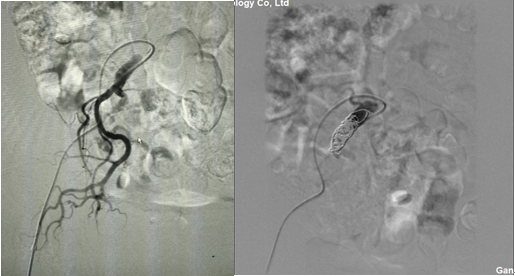

1.根據(jù)3D打印血管制定的手術(shù)方案,腹主動(dòng)脈血管造影,提示動(dòng)脈瘤位置及各血管分支情況。

2、為防止支架釋放后,髂外和髂內(nèi)動(dòng)脈匯合處產(chǎn)生內(nèi)瘺,提前將髂內(nèi)動(dòng)脈栓塞。

3、建立雙股動(dòng)脈通路;雙側(cè)導(dǎo)管交匯于腹主動(dòng)脈